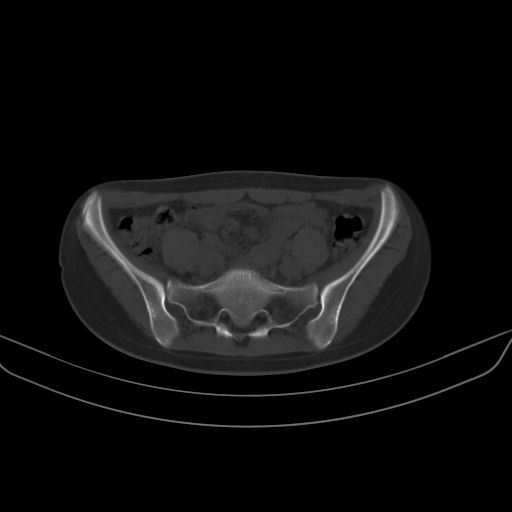

以下是引用子十在2008-7-11 21:12:00的发言:[br]考虑强脊

以下是引用zsl6918在2008-7-11 21:40:00的发言:[br]双侧骶髂关节骨质破坏以下三分之一为主,符合强直性脊柱炎表现

以下是引用zhangzhongshou在2008-7-11 21:41:00的发言:[br]患者是女性,hla-b27抗原(—),首先不太考虑强直性脊柱炎,建议查类风湿因子,骶髂关节改变考虑类风湿性关节炎可能性大,建议进一步检查。